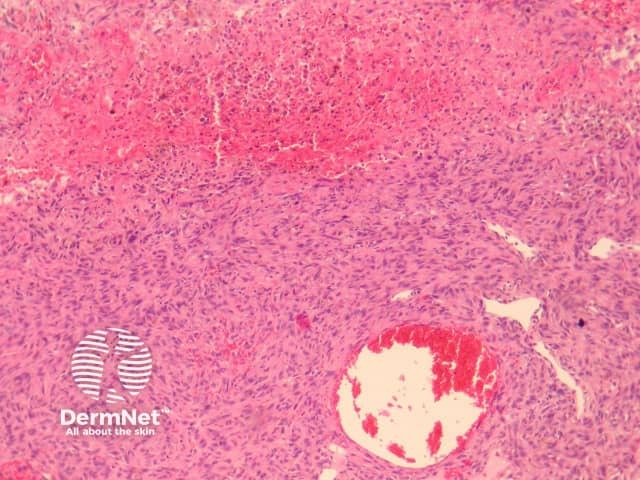

Compared with usual dermatofibroma, cellular dermatofibroma has an increased chance of recurrence following excision and metastasis is reported. Histologically, there is increased cellularity with a swirling, storiform pattern (figures 3,4). Peripheral entrapment of collagen is less prominent in this variant. There may be increased mitoses and extension to the subcutaneous fat, which are associated with more aggressive behaviour. Approximately 10% of cases show central necrosis.

Cellular dermatofibroma may resemble dermatofibrosarcoma protuberans, which can be differentiated by its larger size, increased mitoses and marked involvement of the subcutis. CD34 is positive in dermatofibrosarcoma protuberans and is usually negative in dermatofibroma, although the cellular variant may have focal positivity, especially at the periphery of the lesion. A study of clonal karyotype abnormalities in dermatofibroma found cellular dermatofibromas were more likely to have karyotype abnormalities than common dermatofibromas.

Figure 3

Figure 4